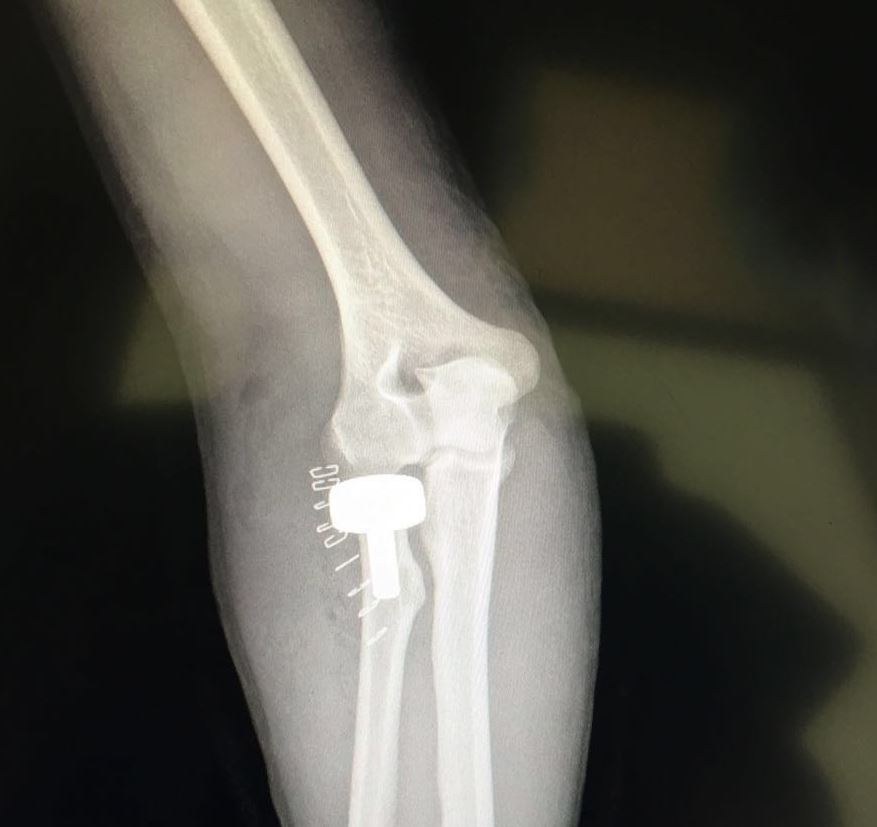

نجح فريق طبي كويتي في الاستعاضة عن عظمة رأس الكعبرة (إحدى عظمتي منطقة الساعد التي توصل المرفق بالرسغ) بمفصل صناعي لوافد آسيوي سقط من علو أثناء عمله.

وأضاف جراغ الذي يشغل أيضا منصب استاذ مساعد في كلية الطب بجامعة الكويت أن العملية التي استغرقت نحو ساعة واحدة كانت معقدة إثر تهشم عظمة (رأس الكعبرة) إلى سبع قطع ما صعب من عملية تثبيت الكسر بـ «البراغي» المعتادة.

وأوضح أن الفريق الطبي تمكن من تبديل العظمة المتهشمة بمفصل حديدي في حين تم الاعتماد على الأشعة المباشرة في غرفة العمليات لتحديد مسار البراغي.

ولفت إلى أن عظمة (رأس الكعبرة) تشكل جزءا كبيرا ومهما من مفصل الكوع، موضحا أنه في حال تهشمها إلى أكثر من ثلاث قطع يكون تبديل المفصل ضروريا.